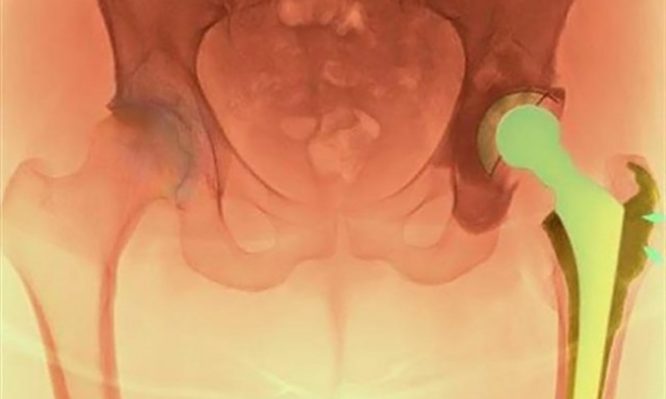

Η ολική αρθροπλαστική ισχίου είναι μία από τις πιο επιτυχημένες χειρουργικές επεμβάσεις στην ορθοπαιδική. Ωστόσο, ένας σημαντικός αριθμός ασθενών υποβάλλεται σε αναθεώρησή της (δεύτερη επέμβαση/επανεπέμβαση) λόγω μηχανικών προβλημάτων (χαλάρωση ή φθορά της πρόθεσης, κακή τοποθέτηση), μικροβιακών λοιμώξεων ή κατάγματος κοντά στην πρόθεση. Σε αρκετούς από αυτούς τους ασθενείς η αναθεώρηση μπορεί να μην έχει τα επιθυμητά αποτελέσματα και έτσι θα χρειαστεί να υποβληθούν σε επέμβαση αναθεώρησης για δεύτερη, τρίτη, ακόμα και τέταρτη φορά. Σημειώνεται ότι, οι επεμβάσεις αναθεώρησης στο ισχίο απαιτούν μεγάλες τομές, σοβαρές κακώσεις στα μαλακά μόρια και έντονη απώλεια αίματος, ενώ συνοδεύονται από αυξημένο ποσοστό επιπλοκών σε σχέση με την αρχική επέμβαση.

Η πρωτοποριακή μέθοδος ASI είναι η πιο σύγχρονη μέθοδος ελάχιστης επεμβατικότητας και χρησιμοποιείται με μεγάλη επιτυχία σε περιπτώσεις που είναι αναγκαία η αναθεώρηση της κοτυλιαίας πρόθεσης. Ορισμένα από τα βασικά πλεονεκτήματα της μεθόδου ASI, είναι η ελαχιστοποίηση του κίνδυνου για μετεγχειρητικά εξαρθρήματα, η εξάλειψη του κίνδυνου για μετεγχειρητική ανισοσκελίακαθώς και η πρόσβαση στην παλαιά πρόθεση και η τοποθέτηση και ο προσανατολισμός της νέας με μεγαλύτερη ευκολία και αξιοπιστία. Παράλληλα, μειώνεται ο χρόνος αποκατάστασης και αποφεύγονται οι επιπλοκές που συνοδεύουν τη μακρά περίοδο ανάρρωσης μετά από εκτεταμένες προσπελάσεις του ισχίου, ενώ δεν χρειάζεται μετάγγιση.